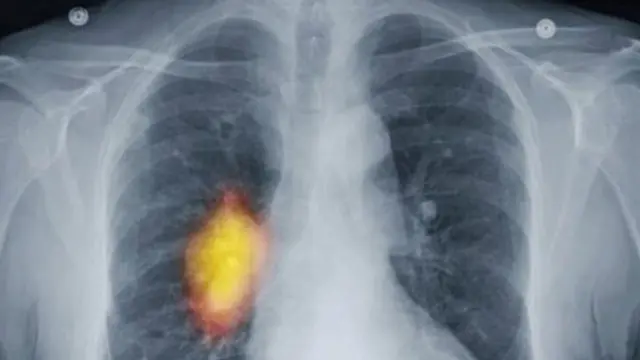

يستطيع مرضى التأمين الصحي في انجلترا الحصول على نتائج التحاليل الخاصة باكتشاف مرض السرطان خلال أربعة أسابيع من إحالة طبيب ممارس لهم بفضل خطط جديدة لتحسين الرعاية الصحية قبل حلول 2020.

وتشخص في انجلترا حاليا إصابة 280 ألف مريض بالسرطان سنويا، ونصف هذا العدد يعيش على الأقل 10 سنوات.